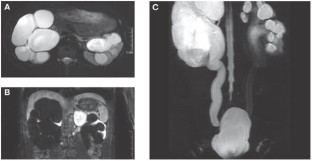

Background A 16-year-old white male with a history of obstructive uropathy presented to a pediatric outpatient clinic with a first syncope. At presentation, he had a hemoglobin level of 220 g/l, a serum erythropoietin level of 27.4 U/l and a serum creatinine level of 200.7 µmol/l (2.27 mg/dl).

Investigations Physical examination, serum laboratory analysis, renal ultrasound, MRI, and 99mTc-MAG3 scintigraphy of the kidneys.

Diagnosis Chronic renal insufficiency caused by obstructive hydronephrosis and accompanied by increased erythropoietin levels of renal origin and polycythemia.

Management Serial phlebotomies and laparoscopic removal of the right hydronephrotic kidney.